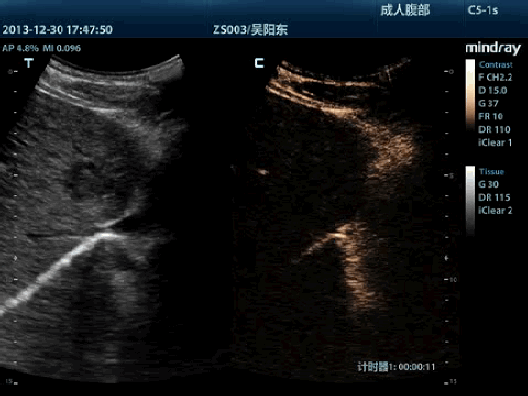

Визуализация с применением контрастных веществ UWN+ (нелинейная визуализация в ультрашироком диапазоне)

Самое большое преимущество УЗ-сканера M9T заключается в поддержке запатентованной Mindray технологии, позволяющей расширить возможности визуализации с применением контраста. Технология UWN+ дает возможность M9T обнаруживать и использовать как вторичные гармоники, так и нелинейные первичные сигналы, создавая изображения более высокого качества.

- Более высокая чувствительность к второстепенным сигналам, меньший расход действующего вещества

- Более длительное время действия активного вещества и более низкие требования к интервалу измерения

- PSHI™ (гармоническая визуализация с фазовым сдвигом)

Изолированная гармоническая визуализация для улучшения контрастного разрешения, обеспечивающая более четкое изображение с превосходным пространственным разрешением и меньшим уровнем шума.